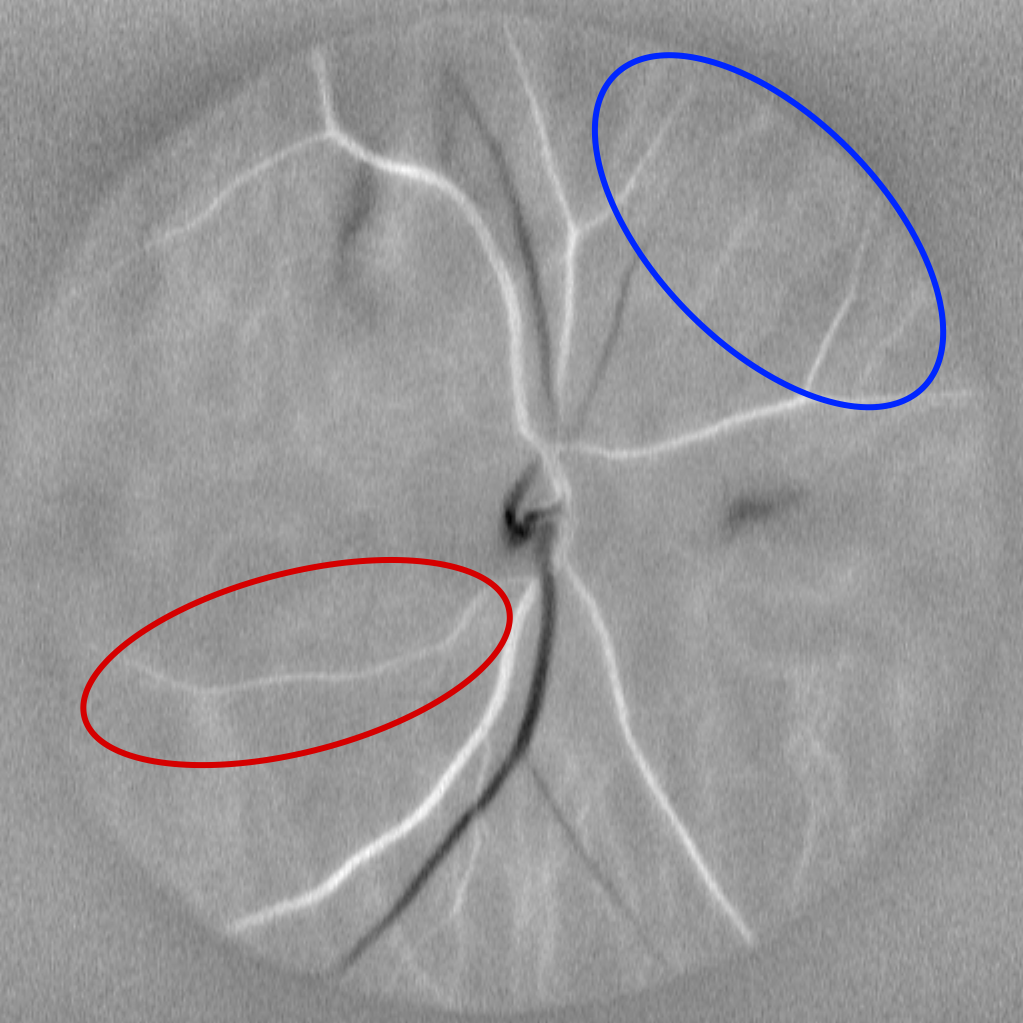

Fig. 1: Different processing of the M0 video. Its average M0 image (b) looses temporal fluctuations, but offers better visualization of the vasculature, including choroidal vessels, not connected to the centered optic disc. Correlation map (c) and Diasys image (d) both convey retinal hemodynamic information, but they respectively better reveal arteries and veins, as shown by red (artery) and blue (vein) selections.

• Finally, artery–vein segmentation is performed by providing the Power Doppler image, the correlation map, and the diasys image (defined as the systolic frame minus the diastolic frame) as inputs to the model. The diasys image and the correlation map convey similar information, but they differ and can be complementary, as shown in fig 1. Fig 3 shows their impact on training.